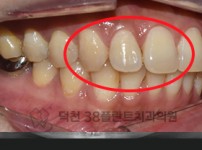

치료전후